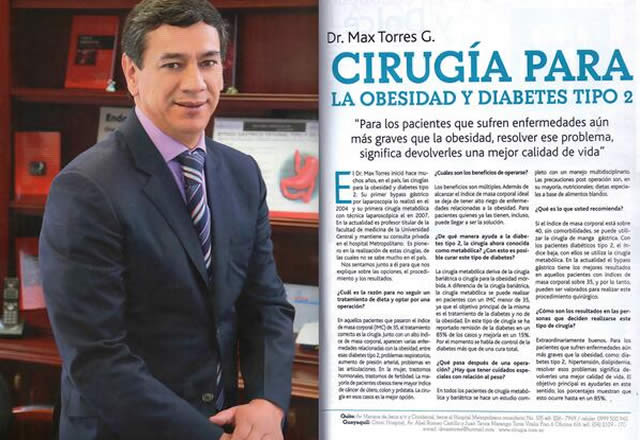

Pionero en Cirugía Robótica en Ecuador

La Cirugía Robótica aplicada a la Obesidad (Dr. Max Torres) Especialista en Cirugía Robótica en Ecuador.